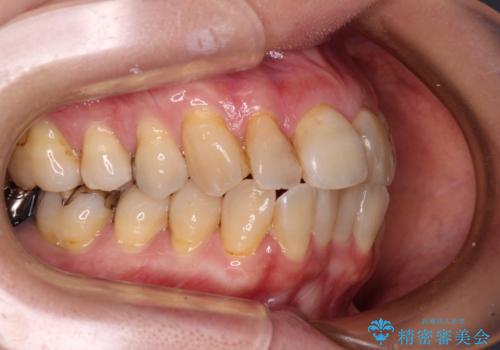

上下前歯が著しく前突している状態であったので、上下左右の小臼歯4本を抜歯し、ワイヤー装置にて矯正治療を行うこととしました。

上顎左側は第二小臼歯に大きなむし歯があったため、通常は第一小臼歯を抜歯するところ、イレギュラーに第二小臼歯を抜歯することとしました。

抜歯する第二小臼歯の後方の歯は神経近くにまで及ぶむし歯があったため、事前に処置をしておき、矯正治療後にオールセラミッククラウンにて補綴治療を行うこととしました。

第二小臼歯抜歯はイレギュラーな治療となるため、アンカースクリューを補助的に使用して、スムーズに治療を行えるように工夫をしました。